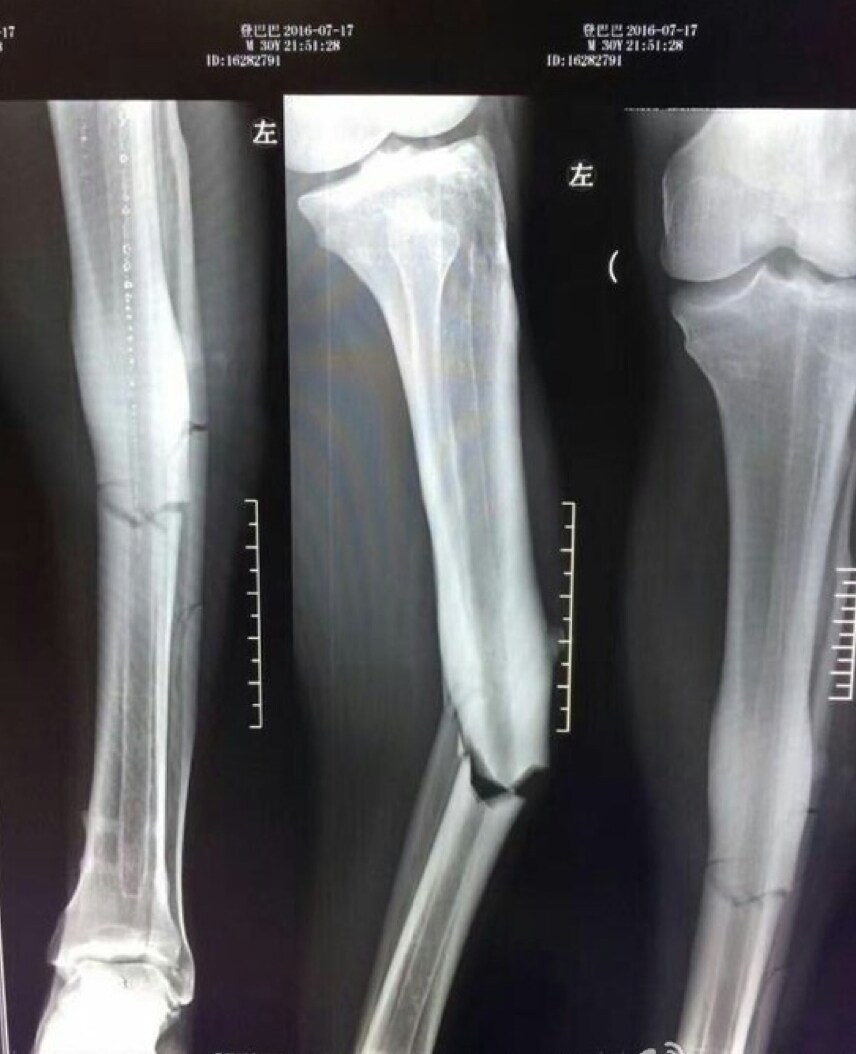

L'infortunio terribile che ha subito, costringerà a un lunghissimo stop Demba Ba. L'attaccante dello Shanghai Shenhua ha rischiato addirittura di chiudere la carriera. Basta guardare le immagini dei raggi x della gamba per comprendere la gravità dell'infortunio.